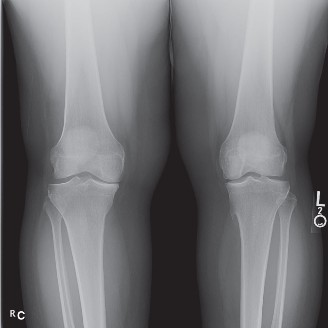

The correct answer is (E). MRI of an ACL tear is shown in Figure 9–2A. The ACL rupture results in a sudden translation of the tibia anterior relative to the femur, resulting in a transchondral fracture (bone bruise) of the anterior lateral femoral condyle and the posterior lateral tibial plateau (Fig. 9–2B).

Figure 9–2 A–B